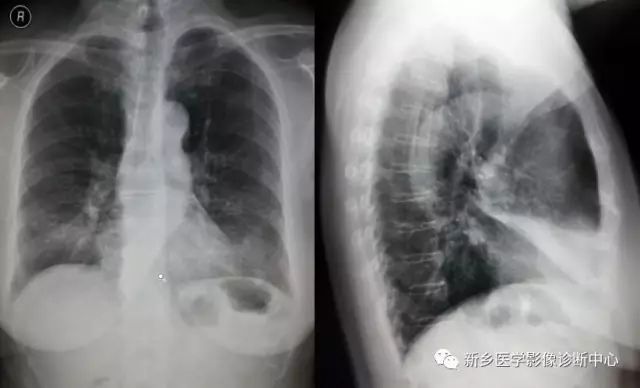

X线表现:

(1) 后前位示 于右心缘看到一个小而密度均匀或略有增高的阴影,上界不超过肺门阴影的中部,以内侧较密,右心缘为其所重叠,这片状密度增高的阴影没有明显的边缘,其外带变淡并逐渐消失,水平裂大多不见,或向下、向内移位,邻近肺野可见代偿性肺气肿。右侧膈肌稍有上升。

(2) 前弓位示 由于不张的右肺中叶,其邻近肺野出现了代偿性肺气肿,所以在正位胸片上常显示不清,采用前弓位检查,使肺门向下倾斜,不张的肺叶的长轴与X线中心线平行,因而投影为一个由肺门向外伸展的三角形阴影,基底部在肺门,尖部向肺野可达胸壁,上下边缘锐利,此为中叶不张的特征。

(3) 右侧位示 自肺门向前下方斜行的带头或条索状致密影,常与心影相重叠,基底部较宽,大多靠近剑突与胸骨交界处,或完全贴靠胸骨下部,水平裂与斜裂移位相靠近,阴影上端不超过肺门。